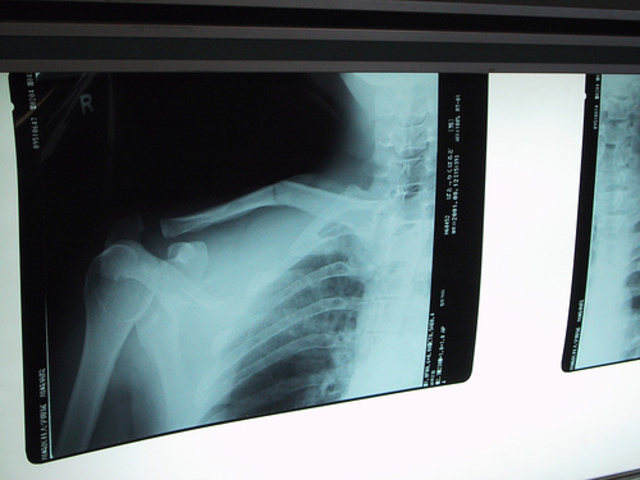

I was playing football and got tackled and broke my right collar bone.

Picture:

X-ray